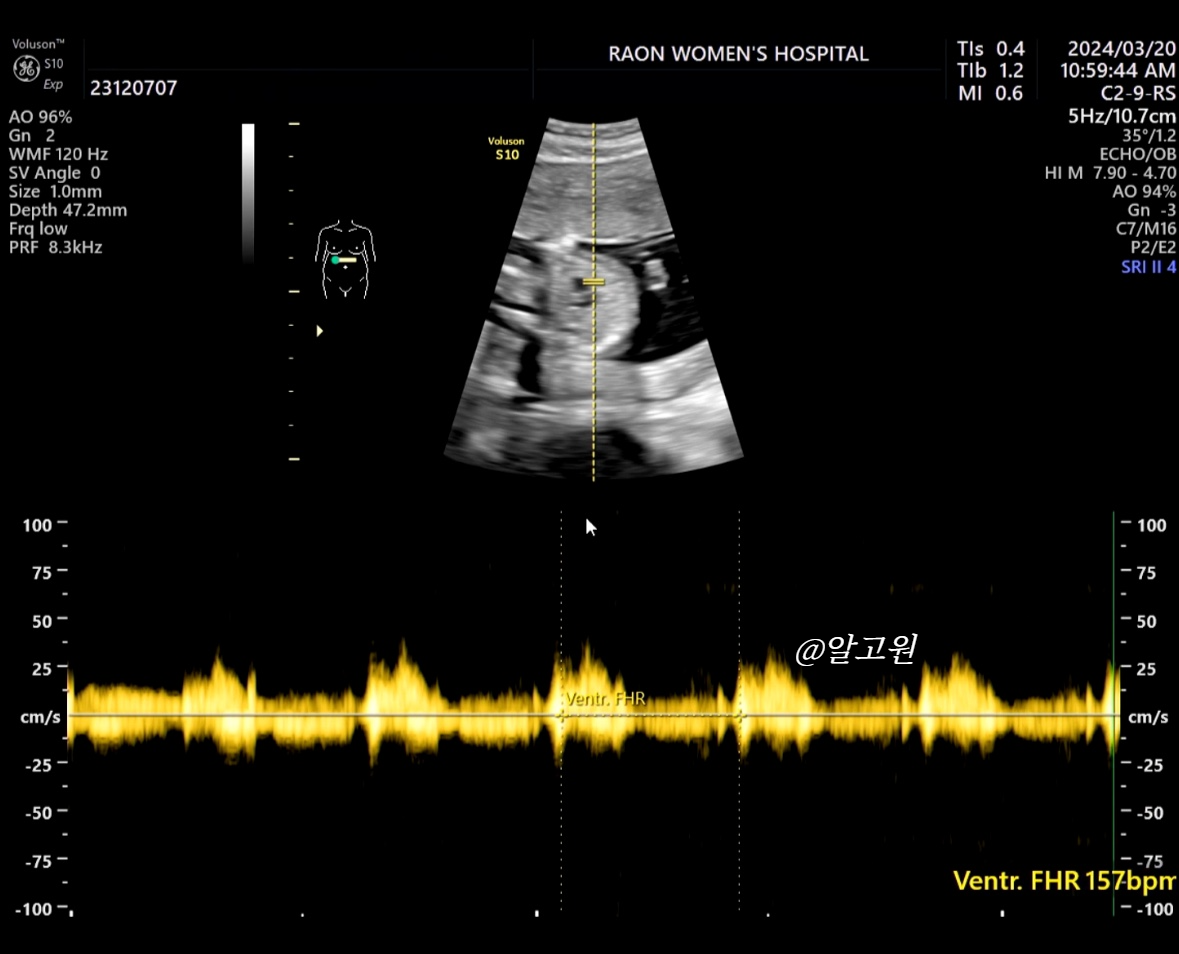

2. 심장 & 장기 체크

- 1차에서 봤던 것처럼 뇌부터 뱃속 장기, 심장박동 소리 등 체크해 주십니다.